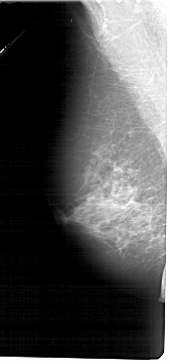

A_1277_1.RIGHT_MLO

RIGHT_MLO LINES 5026 PIXELS_PER_LINE 2206 BITS_PER_PIXEL 12 RESOLUTION 43.5 OVERLAY

FILE: A_1277_1.RIGHT_MLO.OVERLAY

TOTAL_ABNORMALITIES 1

ABNORMALITY 1

LESION_TYPE MASS SHAPE IRREGULAR MARGINS ILL_DEFINED

ASSESSMENT 4

SUBTLETY 5

PATHOLOGY BENIGN